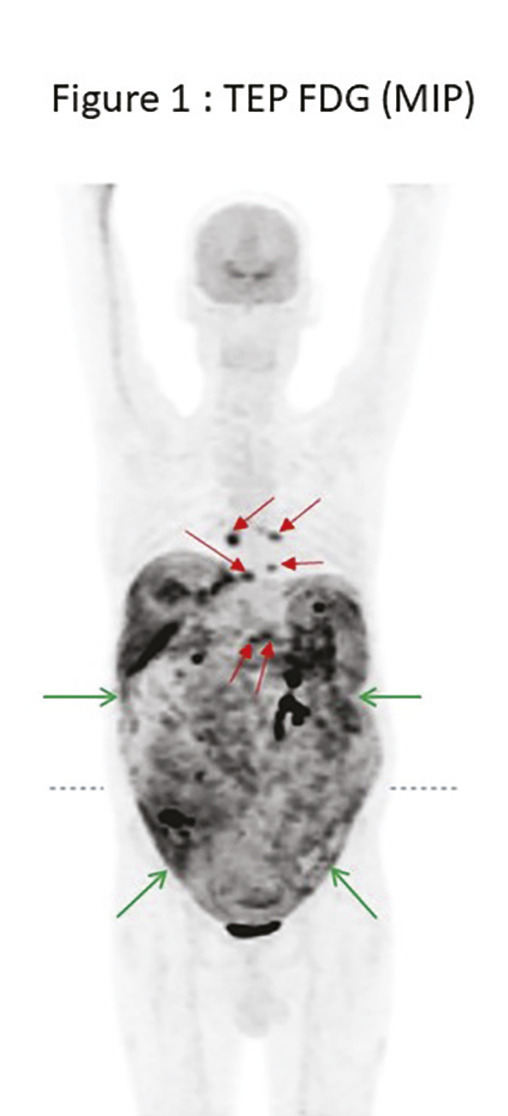

Cet homme de 67 ans était hospitalisé pour décompensation œdémato-ascitique. La tomodensitométrie abdomino-pelviennne montrait un foie cirrhotique avec thrombose portale, ascite abondante et péritoine épaissi prenant le contraste.1 Les leucocytes sanguins oscillaient entre 5 et 12,7 G/L, avec lymphopénie variable et protéine C-réactive à 100 mg/L. Des ponctions d’ascite itératives montraient la présence de lymphocytes et de monocytes avec des neutrophiles inférieurs à 250/mm3. L’examen microscopique direct et les cultures d’ascite étaient non contributifs. Le gradient d’albumine sérum-ascite était élevé (> 11 g/L).2 Le taux d’adénosine déaminase (ADA) était peu élevé (27 UI/L, normale < 24).2 La tomographie par émission de positons au fluorodésoxyglucose (fig. 1 et 2 ) montrait une fixation intense et diffuse du péritoine épaissi (flèches vertes) et des adénopathies hypermétaboliques abdominales et thoraciques (flèches rouges). La cœlioscopie montrait un péritoine multinodulaire. Les biopsies révélaient des granulomes épithélioïdes et gigantocellulaires avec nécrose caséeuse. Mycobacterium bovis était identifiée par tubage gastrique.